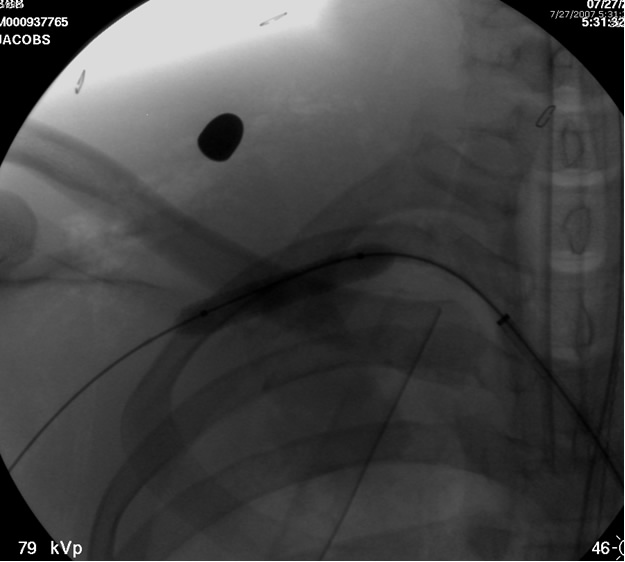

After traversing the vessel with a Glidewire and visualizing the wire conforming to normal arterial profile down into the distal extremity, it is necessary to change out the sheath for a long 8F sheath. It is necessary to advance the sheath into the proximal subclavian artery. To increase support we change out the guide wire for a stiffer Amplatz® (Boston Scientific Corp. Natick, MA) Guidewire extending down into the arm. Next, we perform selective views of the

transected artery visualizing the pseudoaneurysm (Figure 2). A Viabahn covered stent (W.L. Gore & Associates, Flagstaff, AZ) is chosen for the appropriate size of the native vessel being careful not to oversize the stent graft. The stent graft is advanced across the lesion. Selective angiograms through the sheath may be performed to choose correct placement and appropriate landing zones. The stent graft is deployed under fluoroscopic visualization. Next, we utilize an appropriate sized 10 mm low pressure balloon to “iron out the edges” of the stent and bring it up to profile of the artery (Figure 3). Next, completion angiograms are performed to rule out endoleak and complete exclusion of the pseudoaneurysm, as well as to confirm distal runoff to the forearm and palmar branches of the extremity (Figure 4).

![]() |

| Figure 4: Post-deployment of the stent with 10 mm balloon brought up to vessel profile. |